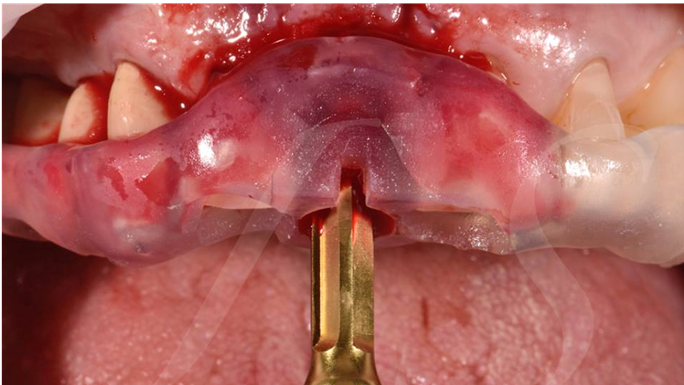

“ One implant /One tooth/ One hour step-by-step

+ associated connective graft ”

Clinical case: EImmediate implant placement & loading of #35 extraction socket with defect

- Courtesy of Dr. Kwang Bum Park, Korea -